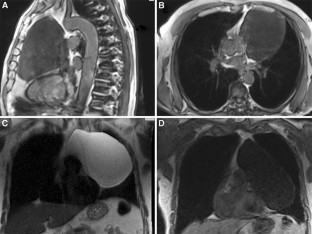

Fig. 2